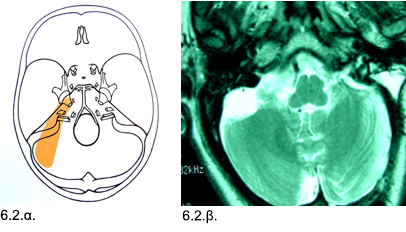

Εικόνες 6.2.α. & 6.2.β. Σχεδιογραφική απεικόνιση της χειρουργικής προσπέλασης προς τον όγκο αποτυπώνεται με σκούρο κίτρινο χρώμα (6.2.α.) και μαγνητική τομογραφία που δείχνει την ολική αφαίρεση του όγκου (6.2.β.).

Ιστορικό: Aσθενής 57 ετών, προσήλθε με μείωση ακοής, εμβοές, αστάθεια και γενικευμένη αδυναμία προοδευτικά επιδεινούμενα κατά τα τελευταία δύο χρόνια. Η κλινική εξέταση έδειξε οριζόντιο νυσταγμό. Κατά τον απεικονιστικό έλεγχο διαπιστώθηκε ένας μεγάλος όγκος διαμέτρου 4 εκ. στον οπίσθιο εγκεφαλικό βόθρο αριστερά. Έγινε οπισθοσιγμοειδική κρανιοτομία και ολική αφαίρεση του όγκου, ο οποίος αποδείχθηκε ότι ήταν μηνιγγίωμα. Η μετεγχειρητική πορεία ήταν ομαλή και η ασθενής δεν ανέπτυξε άλλα νευρολογικά προβλήματα.